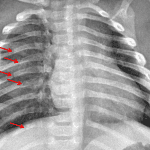

- Acute nondisplaced fractures of the right posterior fourth through seventh and tenth ribs

- Healing nondisplaced fractures of the left lateral fifth and sixth ribs

Acute nondisplaced fractures of the right posterior fourth through seventh and tenth ribs. Healing nondisplaced fractures of the left lateral fifth and sixth ribs. Findings raise the possibility of nonaccidental trauma. Recommend skeletal survey for further evaluation.

No focal airspace disease, pleural effusion, or pneumothorax.

Normal size and contour of the cardiothymic silhouette.